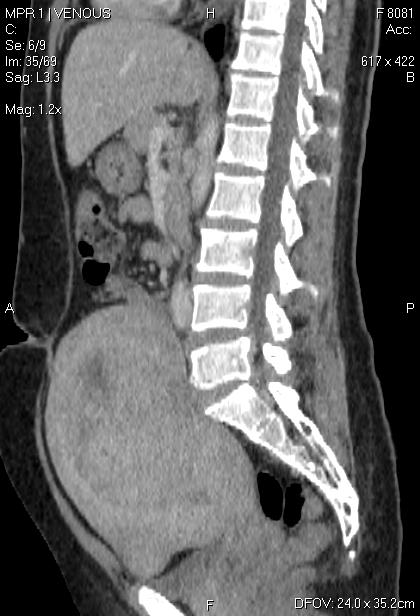

CT-ung thư cổ tử cung

CT-ung thư cổ tử cung 2

CT-ung thư cổ tử cung - di căn gan - tràn dịch màng phổi, ổ bụng

CT-ung thư nội mạc tử cung